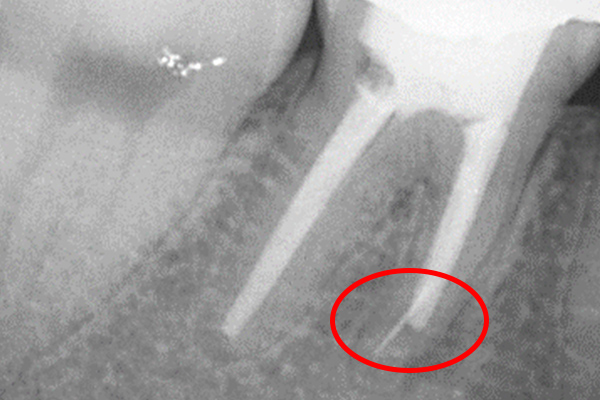

更に、拡大すると歯根破折に加え、器具の破折片も確認できる。

| 治療費 | 破折ファイルの除去費:16,500円 |

| 治療内容 | 破折ファイルの除去 |

| 治療のリスク | 抜歯の可能性 |

| 主訴 | 破折器具除去依頼 |

| 治療費 | 38,500円 |

| 治療のリスク | 除去できない・パーフォレーション |

| 治療費 | CT:11,000円 破折ファイル除去: 49,500円 |

| 治療内容 | 破折ファイル除去 |

| 治療のリスク | 歯根破折・ パーフォレーション |